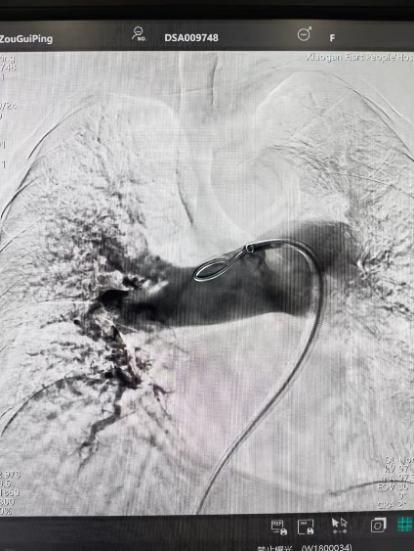

術(shù)前

術(shù)后

手術(shù)在局部麻醉下進行,團隊通過股靜脈穿刺,將專用抽栓導(dǎo)管精準(zhǔn)送達肺動脈栓塞部位,利用負壓抽吸技術(shù)成功清除大量血栓;隨后,在血栓局部精準(zhǔn)灌注溶栓藥物,進一步溶解殘余血栓,恢復(fù)肺部血流灌注;同時,為防止下肢深靜脈血栓再次脫落引發(fā)肺栓塞,團隊為患者置入下腔靜脈濾器,整個手術(shù)歷時約1小時。術(shù)后,鄒婆婆呼吸困難癥狀即刻得到緩解,血氧飽和度顯著提升,右心負荷明顯減輕,目前身體狀況正在逐步恢復(fù)中。